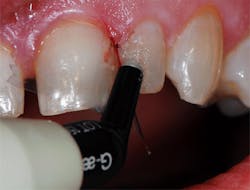

A 62-year-old female patient presented with the complaint of discoloration of a maxillary left lateral incisor. She reported slight, periodic sensitivity to cold on the tooth. Examination disclosed that an old composite restoration was "washing out" (figure 1). The treatment recommended consisted of replacing the defective composite with a new composite.

Figure 1: A defective composite was noted during a hygiene recall appointment, and the patient was advised it needed to be replaced.